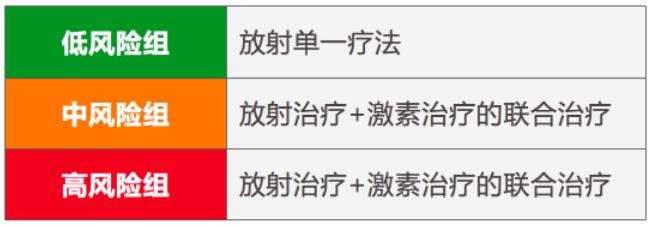

前列腺癌根據病變狀態分為低危、中危、高危三類。低危組單獨使用質子治療,中危組和高危組可聯合激素治療以提高治療效果。